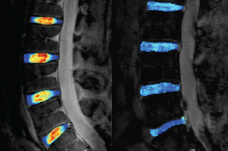

The Musculoskeletal Quantitative Imaging Research (MQIR) group consists of faculty members, postdoctoral fellows, research staff, and medical and graduate students who pursue their passion for teaching and research in quantitative tissue characterization focused on the musculoskeletal system.

Musculoskeletal Quantitative Imaging Research Directions